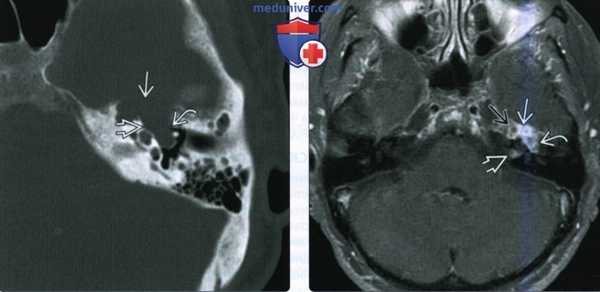

(Слева) При аксиальной КТ в костной окне определяется объемное образование в расширенной ямке коленчатого ганглия с распространением опухоли вдоль переднего барабанного сегмента ЧН VII со смещением слуховых косточек латерально. Наружная поверхность слуховой капсулы истончена ШЛН.

(Справа) При аксиальной МРТ Т1 С+ FS у этого же пациента визуализируется контрастирующаяся ШЛН, расположенная в коленчатом ганглии. Опухоль распространяется вдоль барабанного сегмента ЧН VII и во внутренний слуховой канал по лабиринтному сегменту ЧН VII. Обратите внимание на интрамуральную кисту медиально.